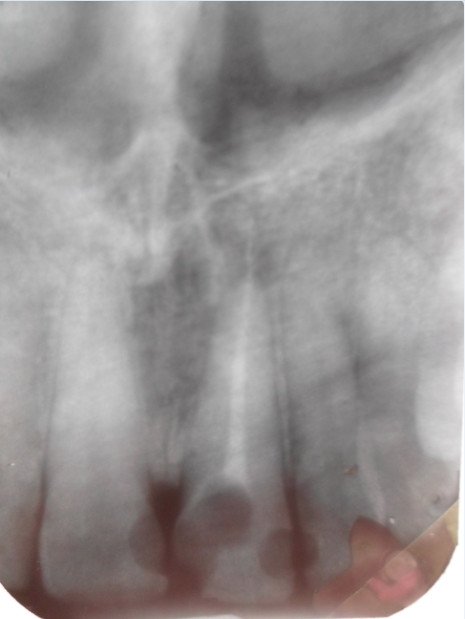

Больше месяца назад мне удалили нерв в переднем зубе (по словам врача из-за хронического периодонтита). Сейчас в этом зубе чувствуется пульсация, зуб не болит, а также после пребывания на холоде отмечаются неприятные ощущения при прикосновении к нему.

Причина как раз в том, что возможно именно сейчас у Вас и развивается хроническое воспаление (периодонтит), причина — некачественное лечение каналов. Также необходимо обратить внимание на наличие дополнительного канала, который не найден, и также данная ситуация может служить причиной воспаления.